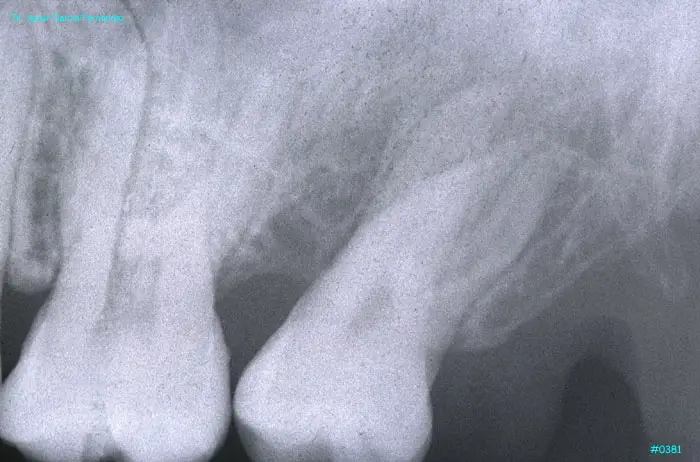

imagen 433